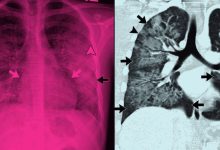

Com desconforto persistente por oito meses, Xuxa optou por operar para se recuperar completamente antes de sua turnê de despedida, marcada para julho de 2026. A estenose foraminal ocorre quando o forame neural, que é o canal por onde os nervos saem da coluna, se estreita, comprimindo as raízes nervosas. Isso pode resultar em dor, formigamento, dormência e fraqueza muscular.

O desgaste natural do disco intervertebral entre as vértebras L4-L5 foi a causa da compressão nervosa em seu caso, resultando em dor lombar intensa que irradiava principalmente para a perna esquerda. Embora frequentemente associada ao envelhecimento, a condição pode afetar pessoas de diversas idades, sendo que, em casos severos, apenas 17% dos pacientes apresentam sintomas.